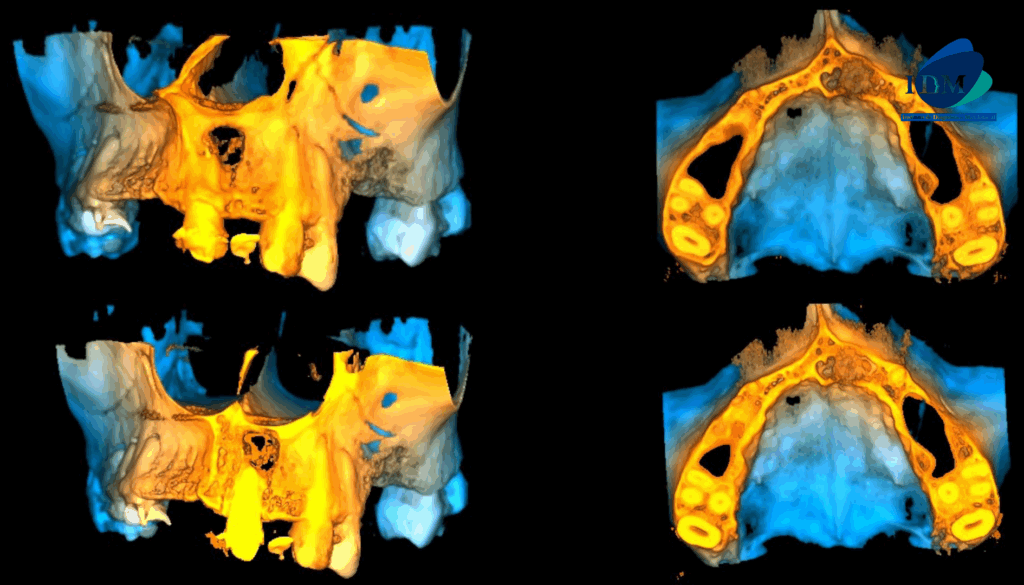

En las reconstrucciones 3D se representa de manera didáctica Lesión Fibroosea (Figura 4).

RECONSTRUCCIÓN 3D

- Lesión Fibroosea